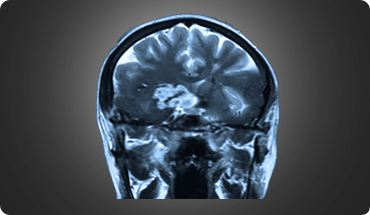

Pituitary tumours are abnormal growths within the pituitary gland, a small gland located near the base of the brain. Pituitary tumours can be either functioning or non-functioning. Functioning tumours secrete pituitary hormones that can lead to a clinical syndrome, while non-functioning tumours are those that can cause a syndrome by not secreting pituitary hormones.